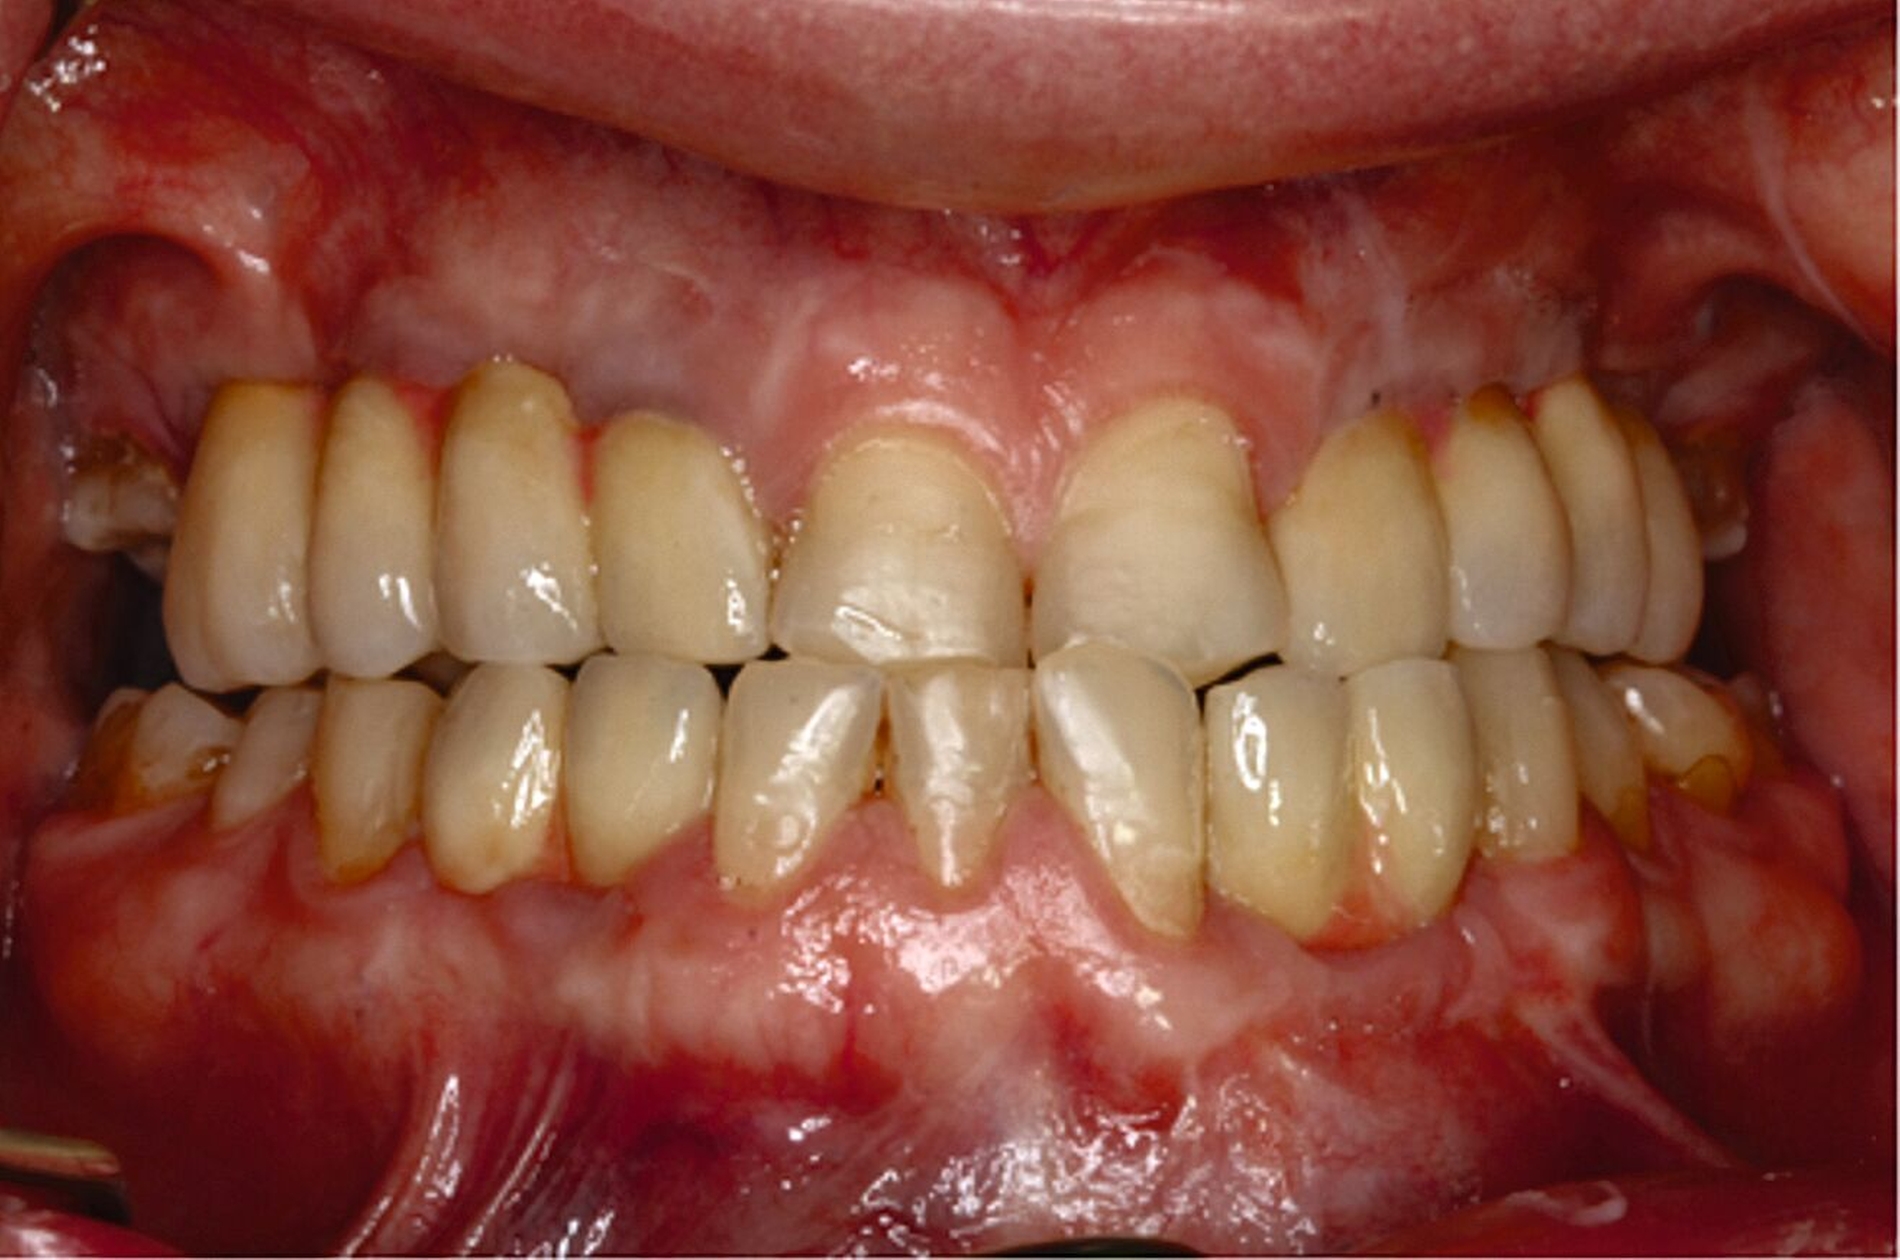

Eine mögliche und indizierte Umstellungsosteotomie wurde vom Patienten abgelehnt. Da seitens des Patienten eine Kopfbissstellung möglich war, wurde eine Bissumstellung und -hebung mit nur noch geringgradigem Vorbiss und anschließender Zahnimplantation in Erwägung gezogen. Begonnen wurde mit einer temporären Schienentherapie zur Neuorientierung der Bisslage (Abbildung 3). Da der Patient die angepasste Bisshebung tolerierte, wurde diese nach Entfernung der persistierenden Milchzähne 55, 53, 52, 62 und 83 temporär mittels einer Valplastprothese (Abbildung 4) als Interimsersatz im Oberkiefer gesichert.

Ausgehend von der neu eingestellten und kompensierten Bisslage des Patienten erfolgte die Entscheidung über das weitere therapeutische Vorgehen. Dabei kamen folgende Behandlungskonzepte in Betracht:

Im Oberkiefer: Implantationen zur Pfeilervermehrung und Teleskopversorgung, alternativ festsitzende Kronen-Brückenversorgungen. Eine Teleskopversorgung allein auf den restlichen natürlichen Zähnen wäre aufgrund der vertikalen Distanz nach erforderlicher Bisshebung nicht möglich gewesen.

Im Unterkiefer: Lückenschluss mit konventionellen Brückenversorgungen mit fraglicher Prognose, alternativ Einzelzahnimplantationen mit Implantatkronen.